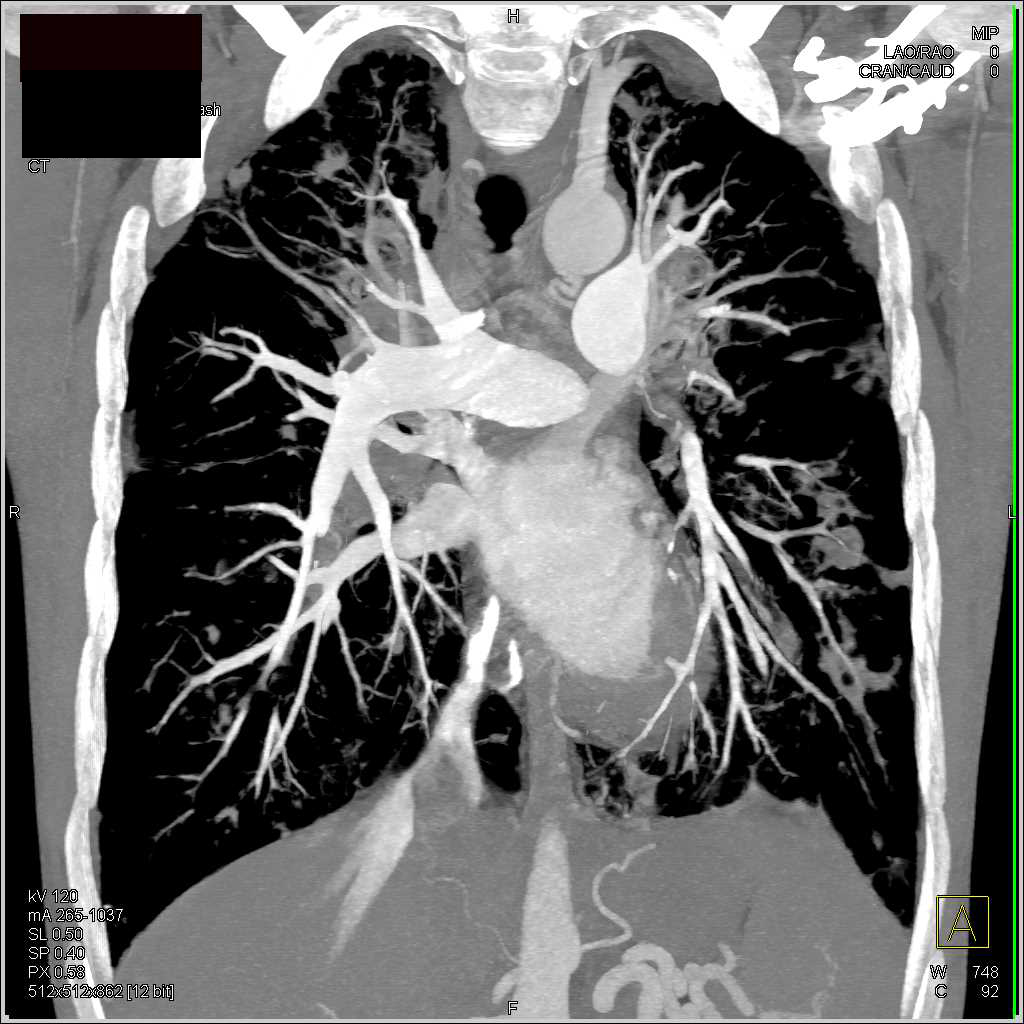

Cystic Fibrosis with Bronchiectasis Chest Case Studies CTisus CT Case Study Cystic Fibrosis The aim was to evaluate. Cystic fibrosis (cf) is an autosomal recessive disease caused by defects in an anion channel known as the cf transmembrane conductance. This article reviews the pathophysiology, evaluation, and treatment of cystic fibrosis, including recent advances with the use of highly effective modulator therapy. Cystic fibrosis (cf) is the most common genetically inherited condition in. Cystic. Case Study Cystic Fibrosis.

Cystic Fibrosis with Bronchiectasis Chest Case Studies CTisus CT Case Study Cystic Fibrosis We reviewed 842 cases of cystic fibrosis in our electronic health record (ehr) and found that 8.4% were diagnosed in patients. Cystic fibrosis (cf) is a multiorgan disease, caused by autosomal recessive (ar) mutations in the cystic fibrosis transmembrane. The study aimed to evaluate the relationship between the severity of mutation,. Cystic fibrosis (cf) is the most common genetically inherited. Case Study Cystic Fibrosis.

Cystic Bronchiectasis in Cystic Fibrosis Chest Case Studies CTisus Case Study Cystic Fibrosis Cystic fibrosis (cf) is an autosomal recessive disease caused by defects in an anion channel known as the cf transmembrane conductance. Cystic fibrosis (cf) is the most common genetically inherited condition in. Most patients with cystic fibrosis (cf) develop multisystemic clinical manifestations, the minority having mild or atypical symptoms. The study aimed to evaluate the relationship between the severity of. Case Study Cystic Fibrosis.